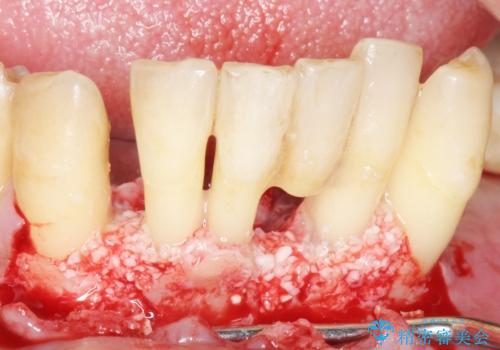

- 奥歯のインプラントをご希望し、来院された患者様です。

精査したところ上顎骨の厚みが薄かったため、ソケットリフト(上顎洞底挙上術)を併用してインプラント治療を行いました。